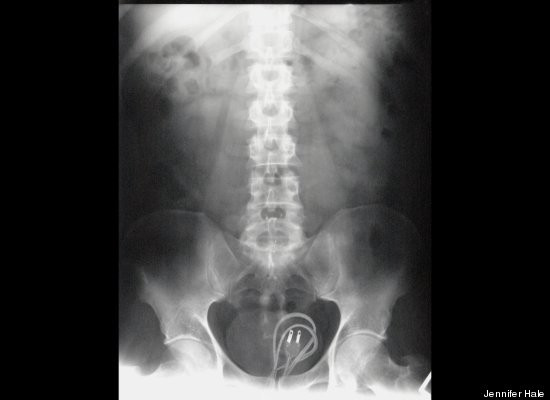

Điểm đặc biệt của cuốn sách là tập hợp 100 câu chuyện về những vật thể lạ bị kẹt một cách khó tin trong cơ thể. Ví dụ như cái kéo, cuộn dây điện hay búp bê Barbie.

Đừng nghĩ rằng người ta chỉ dễ bị hóc với những vật nhỏ, bác sĩ Sindhian đã từng cấp cứu cho một bệnh nhân bị kẹt cuộn băng cát-xét trong bụng.